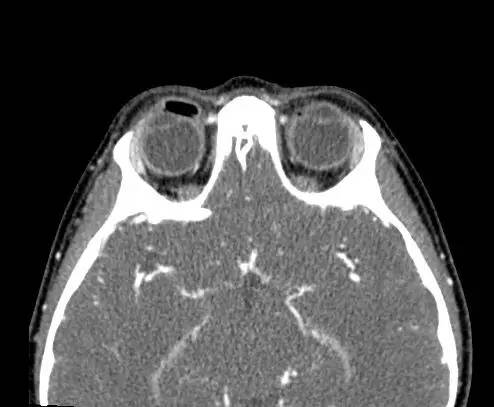

右侧上眼睑软组织肿胀。上眼睑与眼球间可见矩形积气,约1 cmx 0.4 cm x 0.4 cm,并线样影在内穿行。眼球及晶状体正常。眶隔后及眶内软组织无肿胀、血肿或脂肪条纹提示为创伤性。无对比剂外渗。无对急性骨异常。右侧上颌窦粘膜增厚。

【诊断】右上眼睑和眼球间木片存留

There is a piece ofwood between the superior right eyelid and the globe.

CT为评价眼眶创伤的一线方法,可帮助评估眶内异物的存在。木片可能很难与气体及骨折片区分。木片CT的表现取决于其含水量,干松木密度较低,而鲜松木密度高,取决于空气与水的含量。干木因网状基质可以区别于空气。MR对干木的检查可能更敏感,在T1加权图像相对脂肪呈低信号。